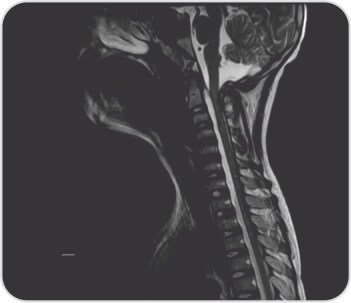

মস্তিষ্কের সাথে পুরো মেরুদণ্ডের এমআরআই দীর্ঘ সেগমেন্টের পূর্ববর্তী এপিডুরাল সংগ্রহ প্রকাশ করেছে যা T2-তে হাইপারিনটেন্স এবং T1-এ হাইপোইনটেন্স ছিল যার লেয়ারিং C2 থেকে D8 স্তর পর্যন্ত প্রসারিত হয়েছে যার ফলে সার্ভিকাল এবং ডোরসাল কর্ডের পশ্চাৎ স্থানচ্যুতি এবং কম্প্রেশন-সম্ভাব্য রক্তক্ষরণ, পোস্টেরিয়র প্যারাস্পাইনাল নরমের মৃদু মচন। সার্ভিকাল অঞ্চলে টিস্যু লক্ষ্য করা গেছে। ল্যাবরেটরি তদন্তে Hb7.5gr%, TLC11, 700/mm3, প্লেটলেট 2.92lakhs/mm3, Rbs 96 mg/dl, সিরাম ক্রিয়েটিনিন 0.5mg%, Bl.urea 37.0 mg%, Serum Na+ 128, S.K, S.3.6+93.0। Cl- 21.90 meq/l মোট বিলিরুবিন 13.70 মিলিগ্রাম% (সরাসরি 8.20 পরোক্ষ 254) SGPT 180u/l SGOT 265.00 u/l Alk ফসফেটেস 6.00, মোট প্রোটিন 2.80 g% (Alb.3.20b.68.0%), 8.0b%। PT 86.8 সেকেন্ড INR > 2.62, APTT 7 সেকেন্ড। HAV IgM অ্যান্টিবডি পজিটিভ: 3; HBsAg, HBeAg, HCV, HIV: প্রতিক্রিয়াশীল নয়; ANA প্রোফাইল নেতিবাচক ছিল। তাকে নিবিড় পরিচর্যা ইউনিটে ভর্তি করা হয়েছিল এবং প্যারেন্টেরাল ভিটামিন কে ইনজেকশন এবং ভেন্টিলেটরি সাপোর্টিভ কেয়ার সহ 3 ইউনিট এফএফপি, 6টি পিআরবিসি পেয়েছিলেন। নিউরো সার্জারির পরামর্শের পরে C2-C5 ল্যামিনোপ্লাস্টি এবং ভর্তির 15 দিনে হেমাটোমা সরিয়ে নেওয়া হয়। 2 তম দিনে, ট্র্যাকিওস্টোমি করা হয়েছিল এবং ধীরে ধীরে ভেন্টিলেটর ছাড়ানো হয়েছিল। পুনর্বাসন কেন্দ্রে বিপ্যাপের সহায়তায় 2.90 তারিখে তাকে ছেড়ে দেওয়া হয়েছিল। কোয়াড্রিপ্লিজিয়া স্রাবের সময় উপরের অঙ্গে গ্রেড 157 শক্তি এবং মোট বিলিরুবিন 68 mg/dl, SGPT 2, SGOT XNUMXu/l সহ টিকে ছিল। দুই সপ্তাহের ফলো-আপে তিনি স্পাস্টিক কোয়াড্রিপ্লেজিয়া - সমস্ত অঙ্গে গ্রেড XNUMX শক্তি, স্থিতিশীল হেমোডায়নামিক্স এবং স্বাভাবিক লিভার ফাংশন পরীক্ষায় আরও উন্নতি করেছেন।